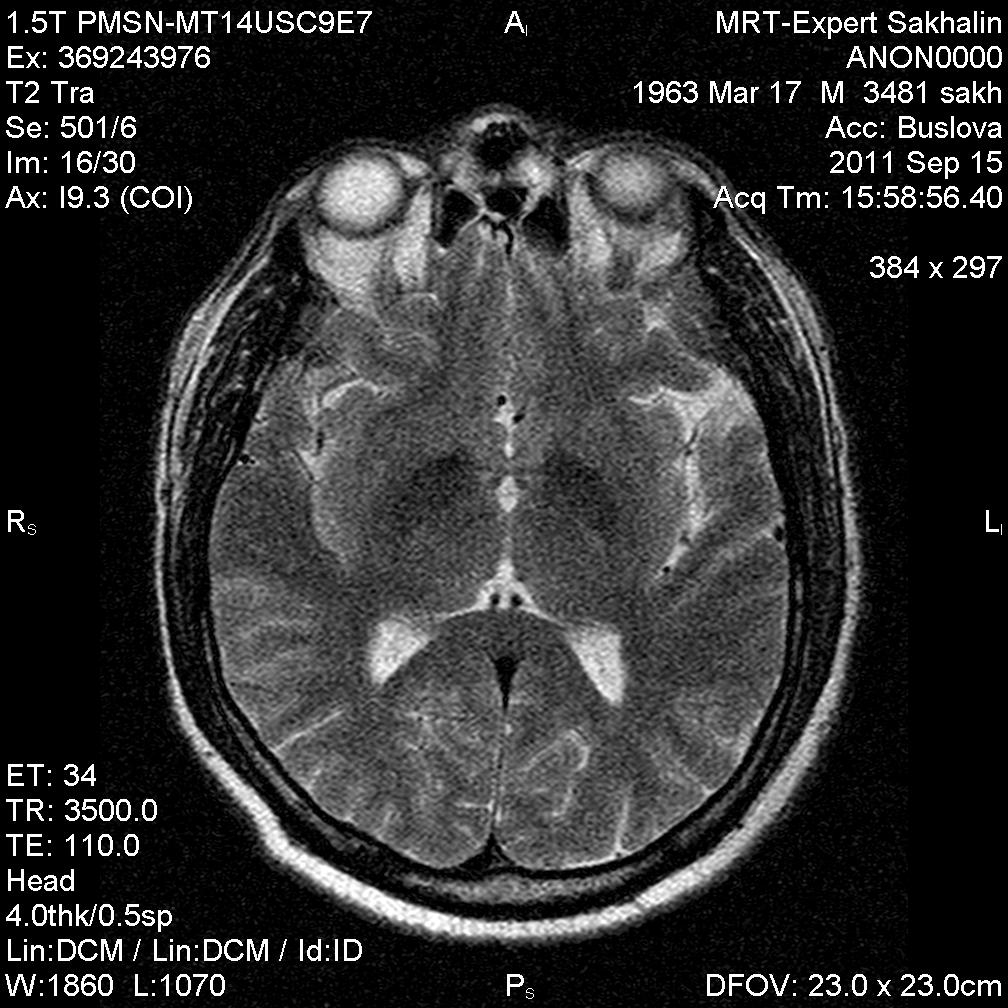

Глаз тигра?

Пациент с жалобами на головную боль.В направлении  дисциркуляторная энцефалопатия.

Первые 3 скана и есть флайер.Не только область базальных ядер ,но левая височная область.

Извиняюсь не распознала флаер. В области полюса левой височной доли арахноидальная киста. Признаков масс- эффекта не вижу. Что касается базальных ядер не уверена что это есть патология. Но еще посмотрю подумаю.

Уж больно бросается в глаза симметричный пониженный сигнал от подкорковых образований. Я так понимаю вы пытаетесь исключить болезнь галлервордена- шпатца?

симметричная дегенрация подкорковых ядер -отложение депозитов железа.